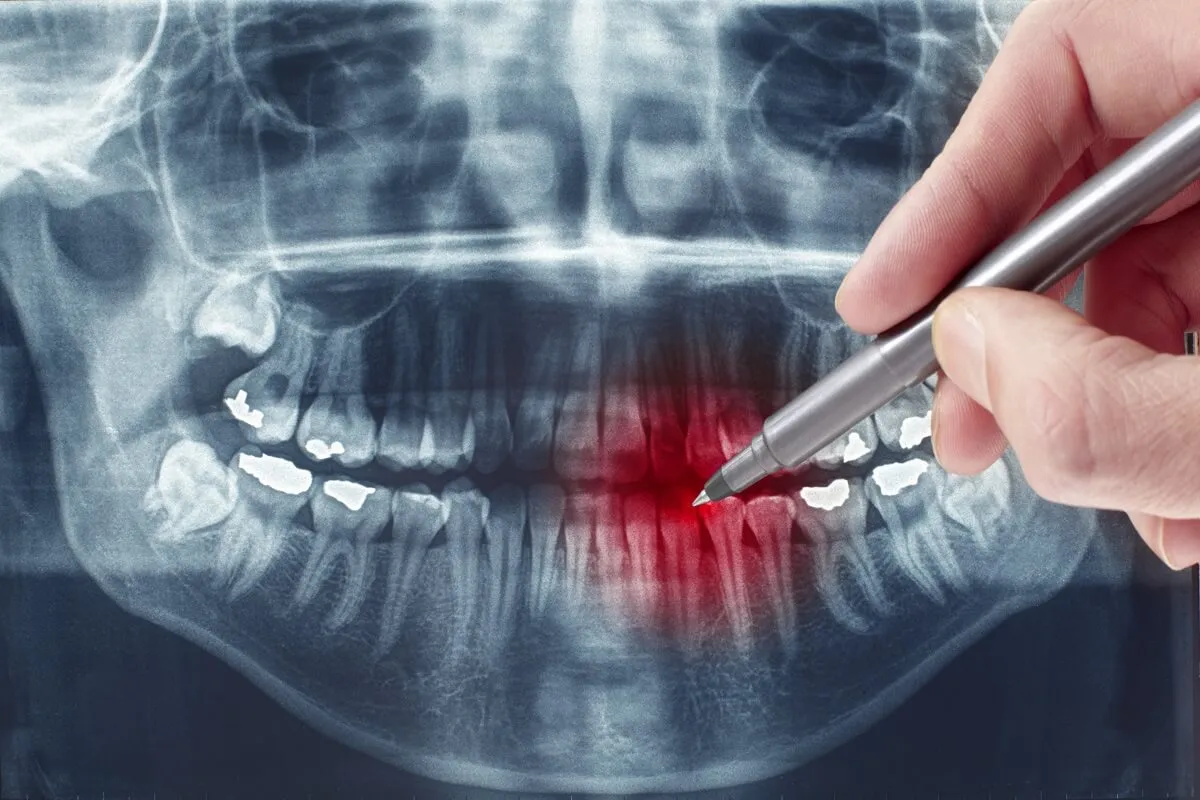

Diagnostyka to podstawa co pokaże zdjęcie RTG i dlaczego jest niezbędne

Kiedy pacjent zgłasza się do mnie z podejrzeniem pozostawionego korzenia, pierwszym krokiem jest zawsze dokładne badanie stomatologiczne. Jednak kluczowym elementem diagnostyki jest wykonanie zdjęcia RTG. Bez niego nie jestem w stanie precyzyjnie ocenić sytuacji. Zdjęcie rentgenowskie pozwala mi nie tylko potwierdzić obecność korzenia, ale co najważniejsze, dokładnie zobrazować jego położenie, kształt, długość oraz stan otaczającej go kości. Dzięki temu mogę ocenić, czy wokół korzenia rozwija się stan zapalny, czy doszło do zaniku kości, a także zaplanować najbezpieczniejszą i najskuteczniejszą metodę leczenia. To podstawa, bez której żadna dalsza decyzja terapeutyczna nie byłaby w pełni odpowiedzialna.